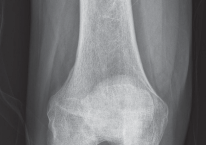

DEFINITION Unicondylar knee arthroplasty (UKA) is a surgical treatment alternative to total knee arthroplasty…